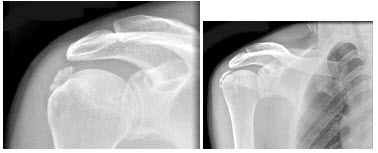

15、单项选择题

男,52岁,肩痛四月余,手臂旋转时疼痛加剧,结合影像,最可能的诊断是()

A.第1~2掌骨